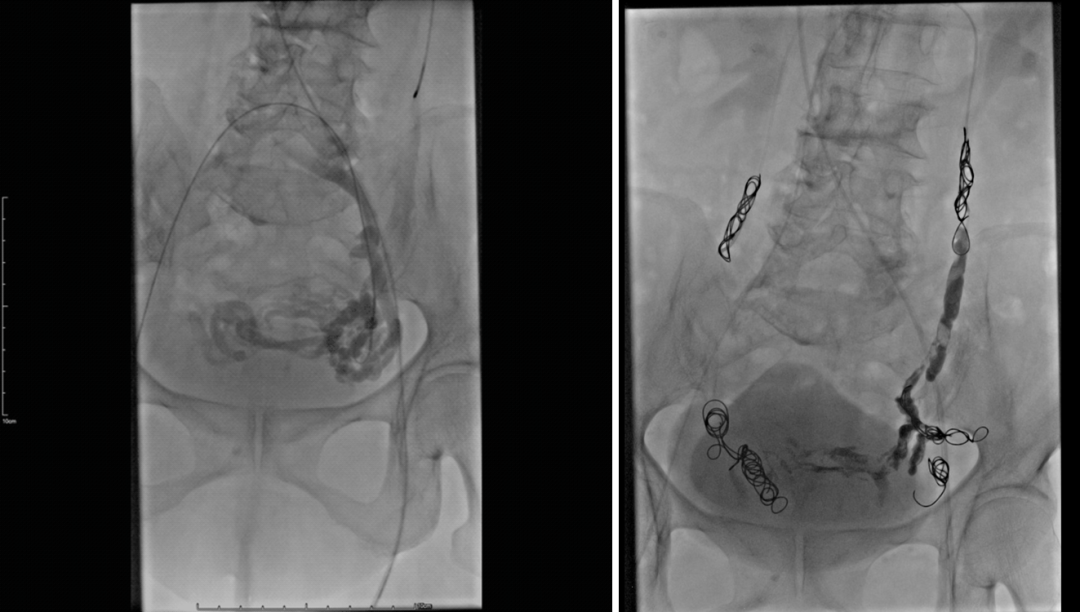

PeVD-髂内静脉同期栓塞

症状性PEP需要同期处理

中山经验:“节约型三明治技术”

Sandwich技术优化-节约版

GLUBRAN替代Onxy;

双股静脉入路:可调弯鞘解决反流支;

减少可控圈以及微导管使用;

示例(D-IIV)

示例(LOV+LCV)

节约型三明治技术--中山三板斧